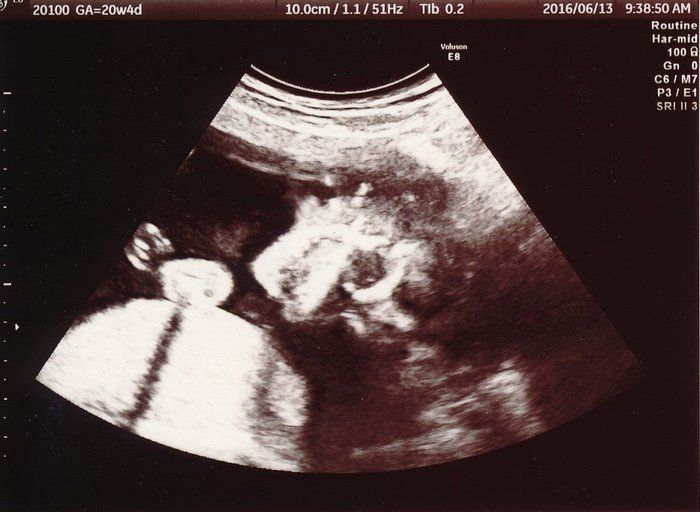

【妊娠20週】赤ちゃんのエコー写真・超音波写真まとめ

ママライターのみなさんの妊娠出産体験談から妊娠20週の赤ちゃんのエコー写真を集めました。

前回と今回の妊婦検診の間に、実は子宮の硬直と出血を起こして、自宅で安静している期間がありました。その間は、おなかの痛みと、絶え間なく頭に浮かぶ不安に耐える日々…。そのため、このエコー画像で元気な赤ちゃんの姿を確認した時は、体の奥が温かくなったのを記憶しています。顔に手を添える様子がほほ笑ましく、おなかを触りながら何度も見返しました。先生から「無理しない程度に、通常の生活に戻っていいよ」と言われました。